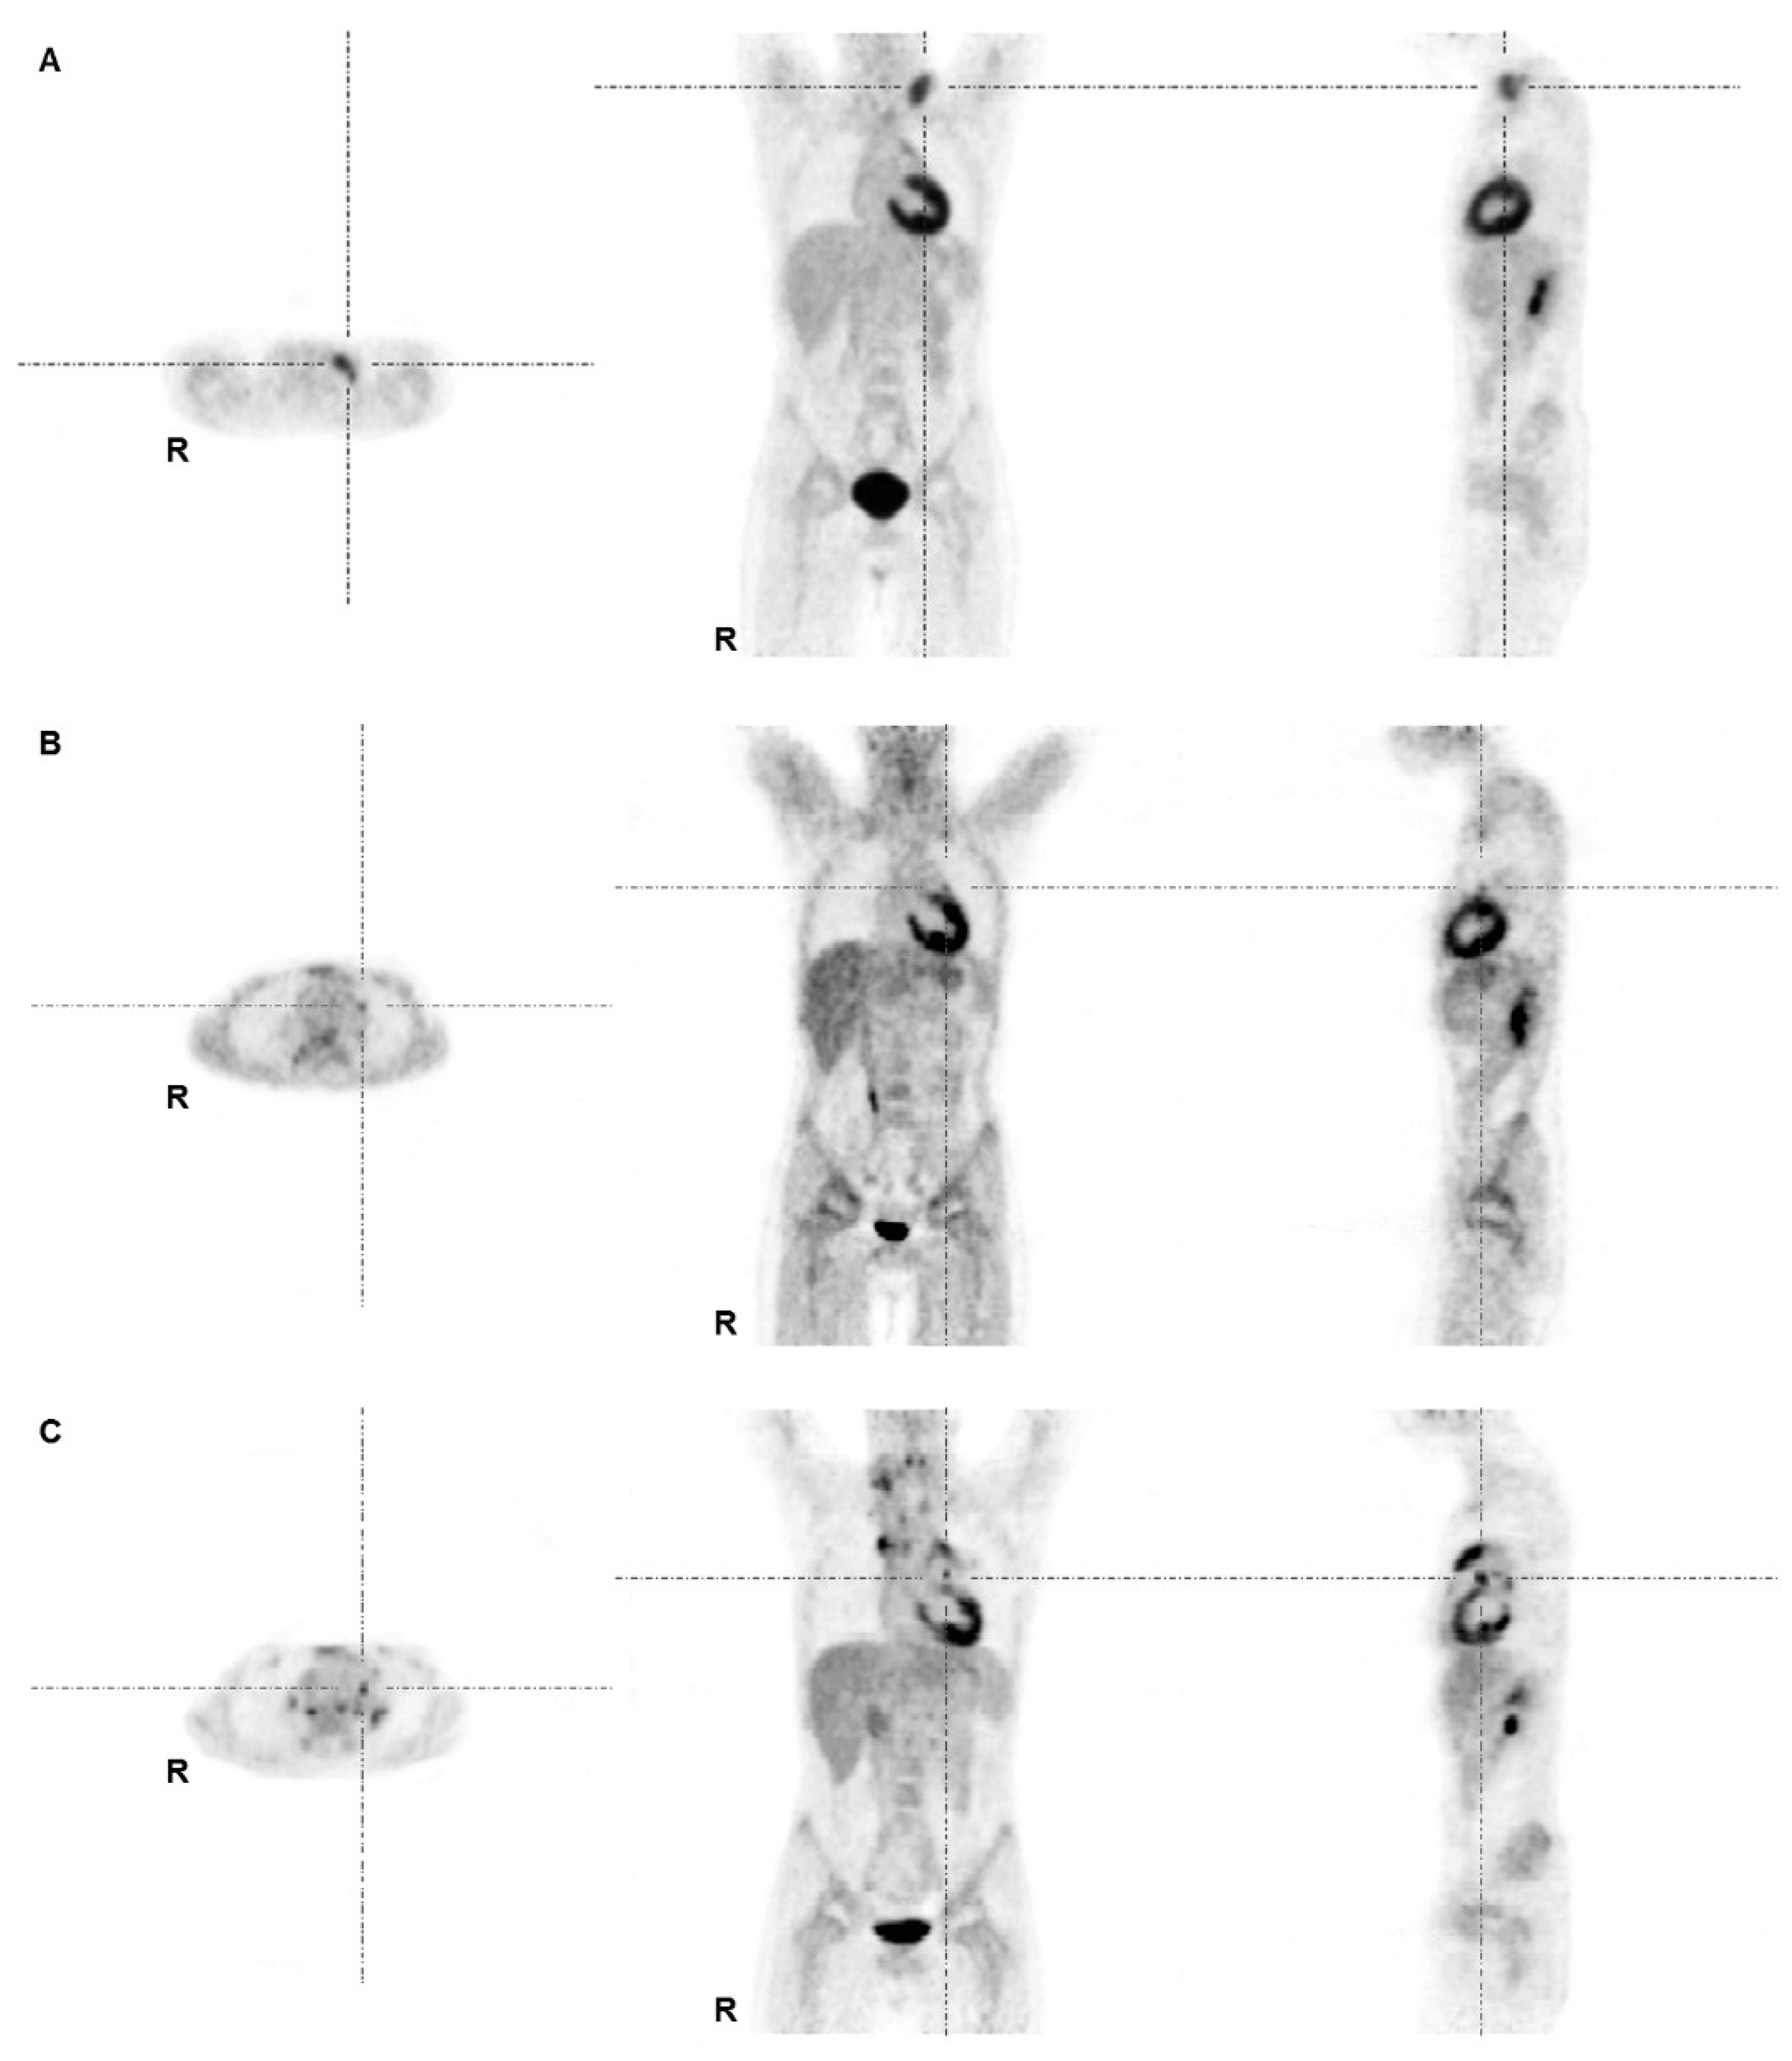

Диагностика лимфомы Ходжкина с помощью ПЭТ и КТ